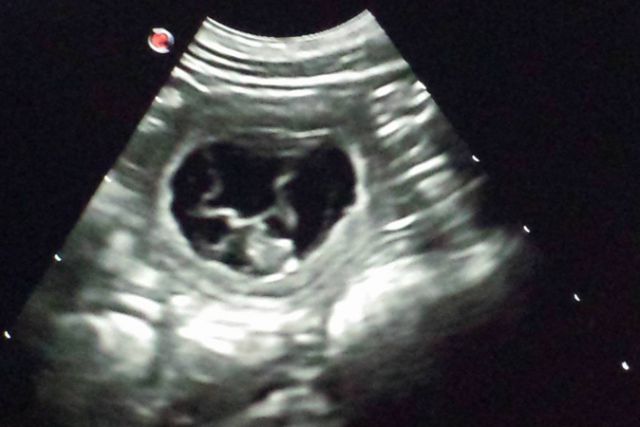

23.01.2017 seit heute ist es offiziell – Hedlund ist tragend!!